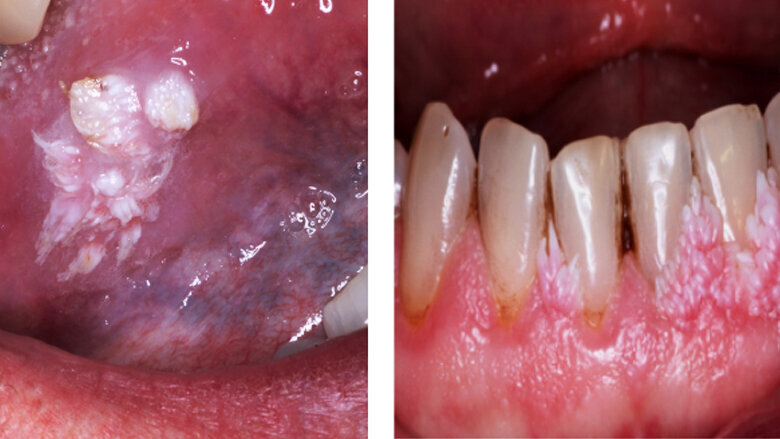

Fig. 3. Condilomas. Son lesiones que se pueden presentar en la mucosa oral, su apariencia es blanda con una superficie parecida a la coliflor.

Fig. 6. Verrugas y condilomas. Los pacientes con SIDA suelen presentar múltiples lesiones de VPH en mucosa genital y bucal, asociadas a inmunosupresión.

Son lesiones que se pueden presentar en la mucosa oral, su apariencia es blanda con una superficie parecida a la coliflor. Su color es rosado y no blanco ya que no está queratinizado. Su forma de contagio es venérea o por autoinoculación (Fig. 3).

Los pacientes con SIDA suelen presentar múltiples lesiones de VPH en mucosa genital y bucal, asociadas a su nivel de inmunosupresión (Fig. 6).